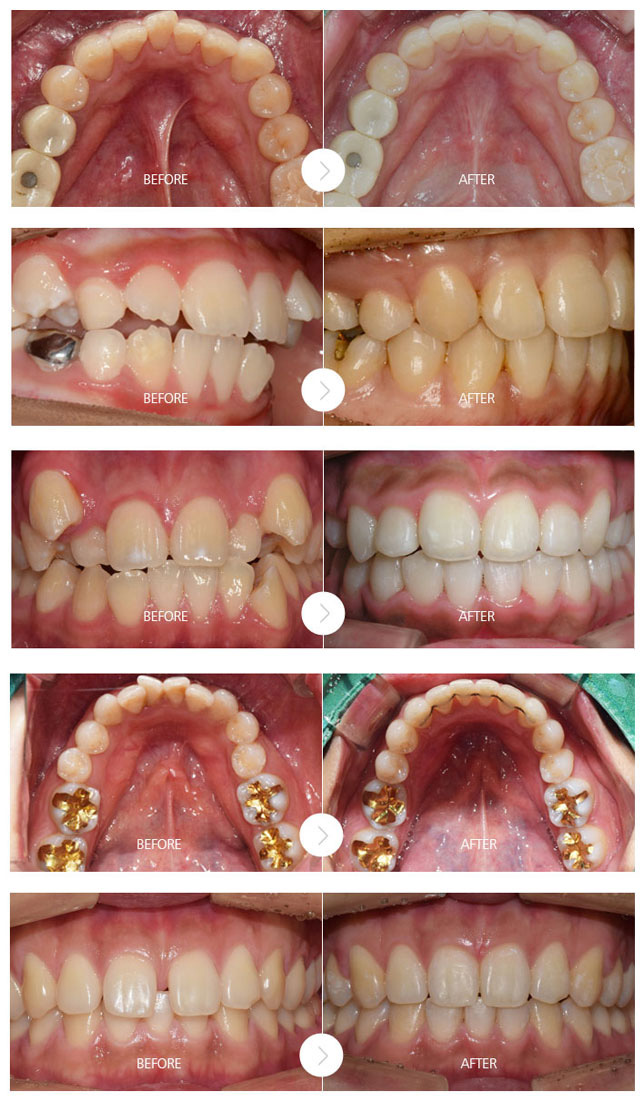

치과 치아교정 백년치과 디지털 교정 교정장치 재수술 임플란트 장치별 교정종류 온라인 상담 치아교정 전후사진 디지털 치아교정